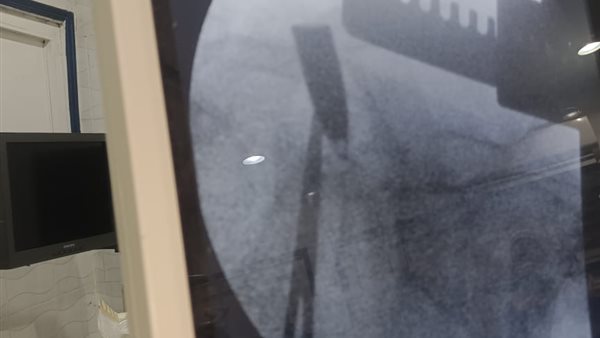

صورة من الاشعة للطبيب

صورة من الاشعة للطبيب المصاب بقنا

أكد مصدر طبى بمديرية الصحة بقنا أن الطبيب المصاب بطلق نارى أصيب في الكتف الأيسر أدت إلى كسر في الضلع الرابع الأيسر وتهتك في نسيج الرئه اليسري وتجمع دموي حول الرئه اليسري وتم إيقاف النزيف وتفريغ التجمع الدموي وإصلاح تهتك الرئه وجاري غلق الجرح دون استخراج المقذوف حيث أنه مستقر خلف عظمة لوح الكتف الأيسر بين العضلات